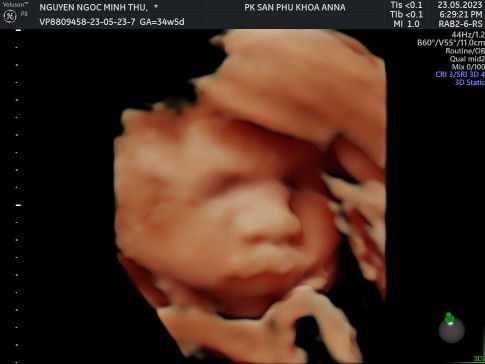

Đọc thêmhình ảnh k rõ lắm. mình siêu âm 3.5kg 40 tuần mà sinh ra cũng có 3.1kg bé xíu. k mũm mỉm lắm nha

dạ 2 ký 3